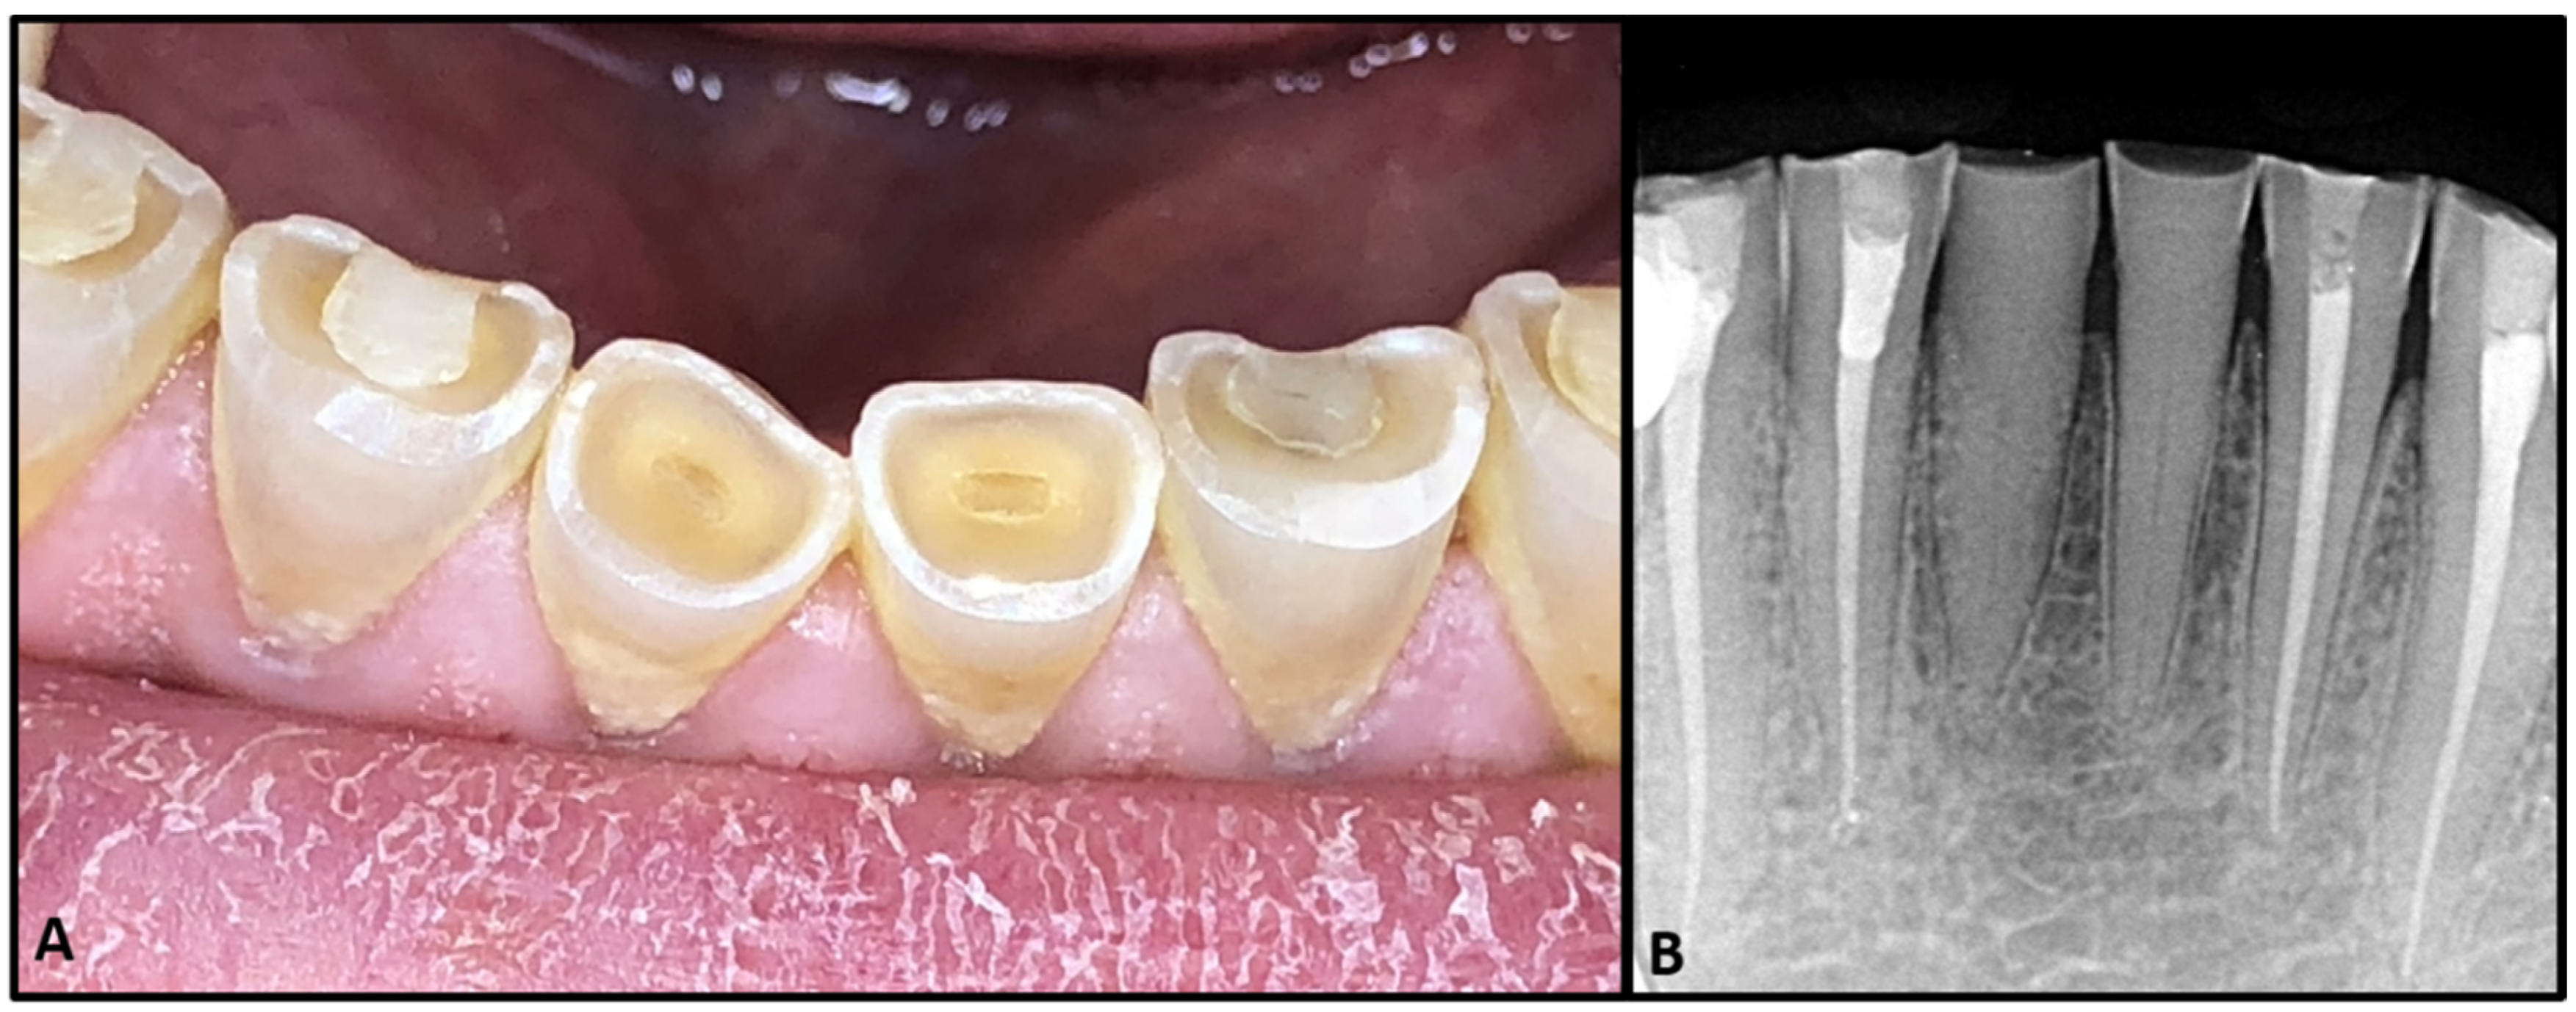

2. Case Report